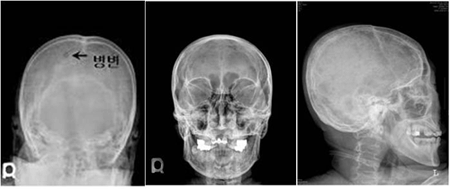

[ 다발골수종 환자의 두개골 X선 ]

다발골수종의 진단을 위해서는 혈액 및 소변 검사와 함께 골수검사를 시행하여 혈액 및 소변에서 검출되는 비정상 단클론단백(M 단백)의 확인과 함께 골수 내 클론성 형질세포를 확인하게 됩니다. 채취된 골수를 통해 다발골수종의 진단뿐만 아니라 염색체와 유전자 검사를 시행하여 향후 질환의 경과 및 예후에 대한 정보를 얻을 수 있습니다. 또한 단순 방사선 검사(X-ray) 및 전산화 단층 촬영(CT)이나 자기공명영상(MRI)와 같은 영상학적 검사를 통해 종양이 발견되는 경우 조직 검사를 통해 진단하기도 합니다.